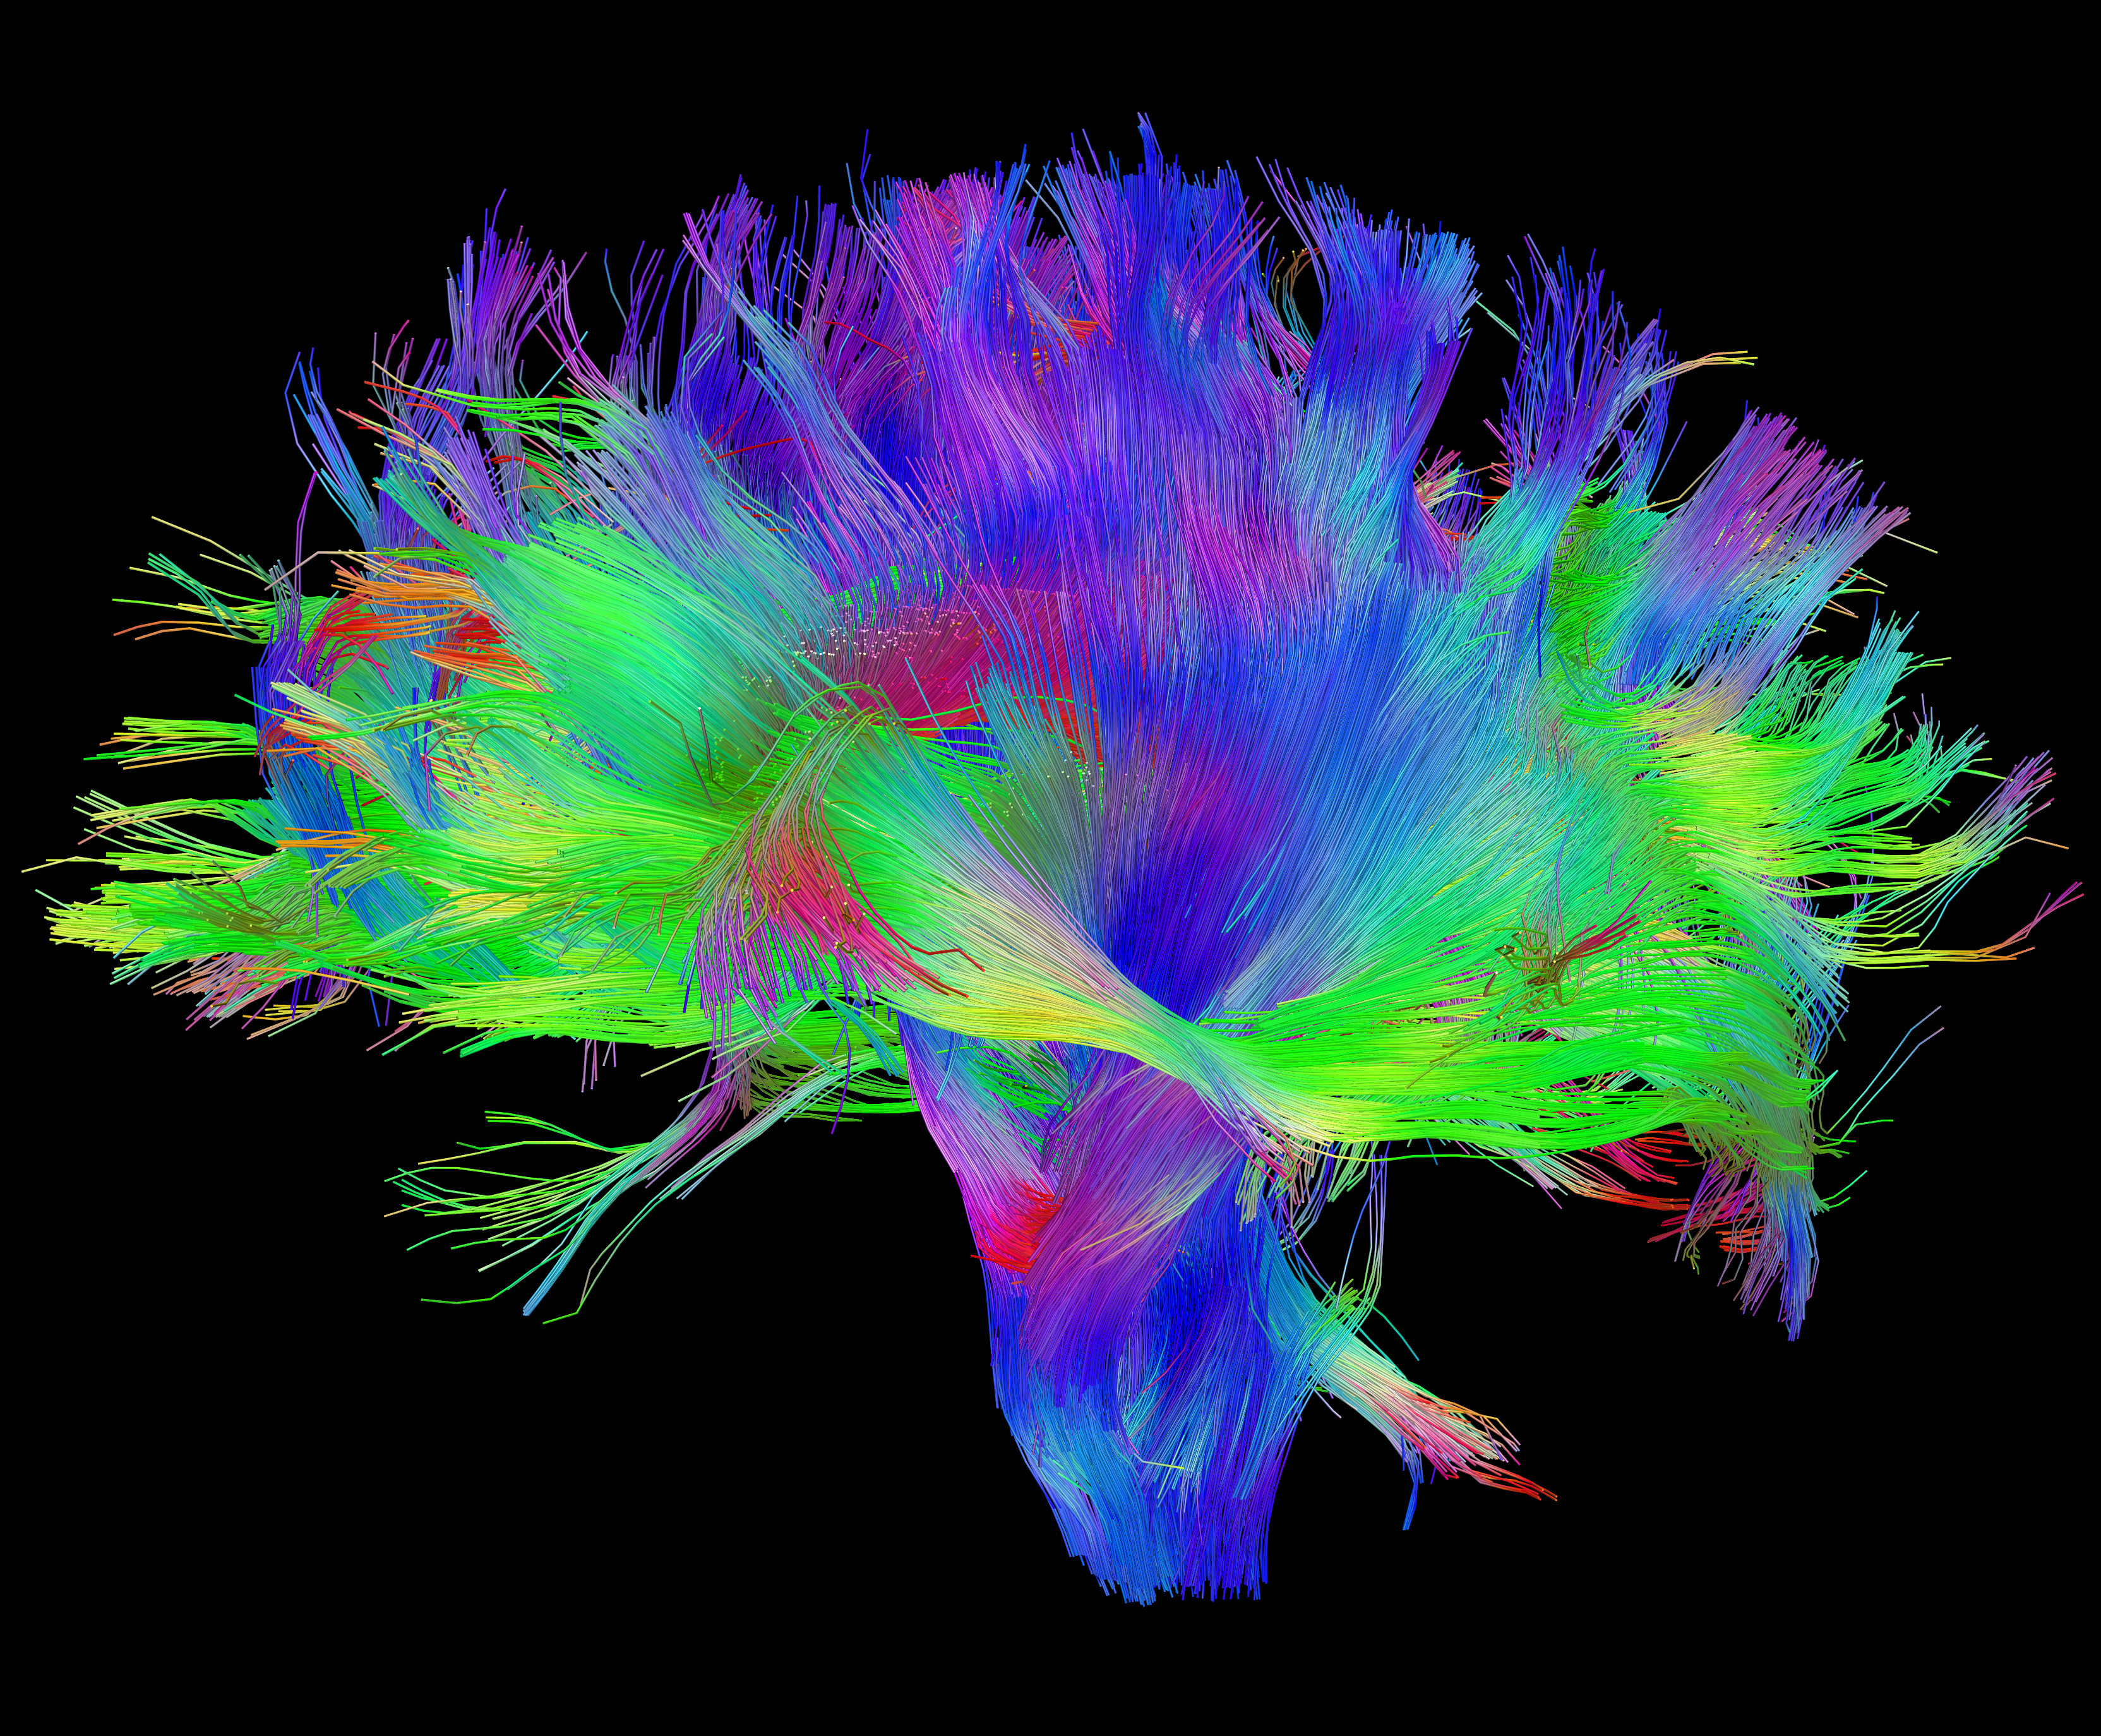

3. DTI: നാഡീസന്ദേശങ്ങളെ ഇതരഭാഗങ്ങളിലെത്തിക്കുന്ന, ‘ആക്സോണുകള്‍’ എന്ന, നാഡീകോശങ്ങളുടെ നീളന്‍വാലുകളുടെ വിന്യാസവും പരസ്പരബന്ധവും വ്യക്തമാക്കുന്നു (ചിത്രം 3).

(ചിത്രങ്ങള്‍ക്കു കടപ്പാട്: ചിത്രം 1: neuroshrink.com ചിത്രം 2: neurocenter.unige.ch ചിത്രം 3: Human Connectome Project ചിത്രം 6: ibtimes.co.uk ചിത്രം 7: wikimedia.org ചിത്രം 8: tremorjournal.org ചിത്രം 9: kids.frontiersin.org ചിത്രം 11: Principles of Biochemistry)